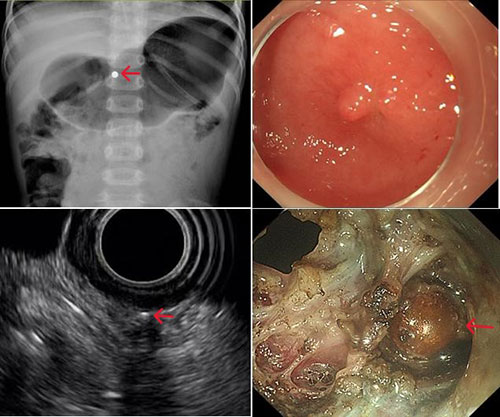

手术团队首先通过超声内镜判断位置,发现残留的磁力珠已进入胃壁外的腹腔内。磁力珠因为在胃内存留时间较久,相互吸引的情况下穿透胃壁进入腹腔,被小网膜包裹。在儿科杨敏主任、内镜中心刘婉薇主任及胃肠外科王俊江主任的指导下,制定了胃全层切开术+腹腔异物取出术的方案。

医生团队通过胃镜进入胃腔,在超声内镜辅助下对磁珠进行定位,通过精密的操作对胃壁全层切开,进入腹腔。因发现磁力珠被胃小网膜包裹,再逐步分离暴露磁力珠,用异物钳为患儿成功取出了体内的磁力珠。最后,通过内镜下金属夹,闭合胃壁的创面。多学科团队在术中共同为患者小琳保驾护航,最终通过超级微创内镜技术为患儿成功取出了体内的磁力珠,小琳体表无任何伤口。李跃副教授介绍,“超级微创”与常规方法对比,患者的手术创伤、手术时间、住院时间、住院费用均明显降低。

红色箭头为磁力珠位置